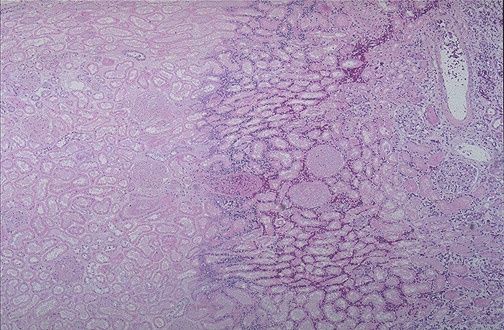

Image 3.3

The low power microscopic appearance of the renal lesion is shown here.